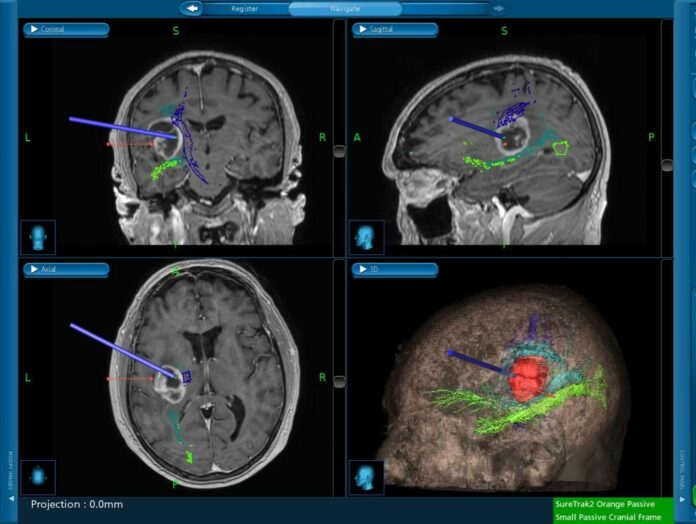

Grazie all’ausilio di avanzate tecnologie diagnostiche, di cui è dotato l’ospedale, è stato possibile ricostruire graficamente, in 3D, tutti i flussi funzionali interni al cervello.

Tale esame, chiamato “Trattografia”, è stato poi importato su un sistema di “Neuro-Navigazione” (modello Stealthstation S7 di marca Medtronic, famosa azienda americana del settore, in dotazione all’ospedale) che ha guidato i chirurghi durante l’atto chirurgico al fine di poter rimuovere tutto il tumore evitando le zone del cervello che svolgono una funzione particolarmente importante (come parlare).

Lo studio funzionale del cervello è stato, poi, ripetuto dopo l’intervento chirurgico e, comparato col precedente, ha permesso di verificare non solo che il tumore è stato del tutto rimosso ma, altresì, che nessun deficit permanente è rimasto al paziente.